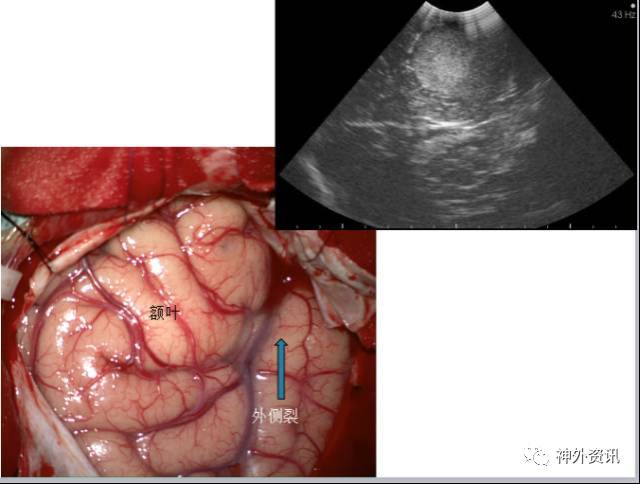

岛叶解剖

岛叶血供

术前B超

手术过程